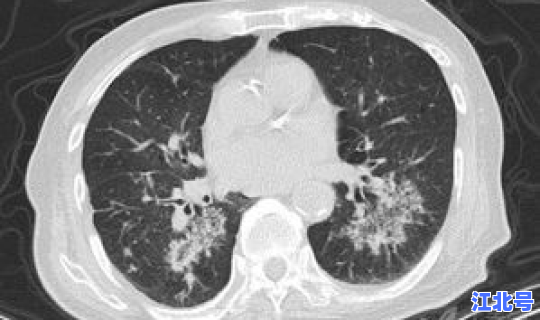

青岛市疫情防控专家组组长 、青岛市疾病预防控制中心副主任张华强说 ,本次疫情中的确诊病例不是在社区中发现,而是在医院筛查中发现,并且病例已立即转入定点医院隔离治疗 。

“鉴于目前社区传播的风险较小、尚未发现社区确诊病例 ,按照科学精准的原则,将青岛市胸科医院所在的楼山后社区定为中风险区域,对区域内的居民根据暴露风险给予隔离或健康管理措施。青岛市的其他区域风险等级不变。”